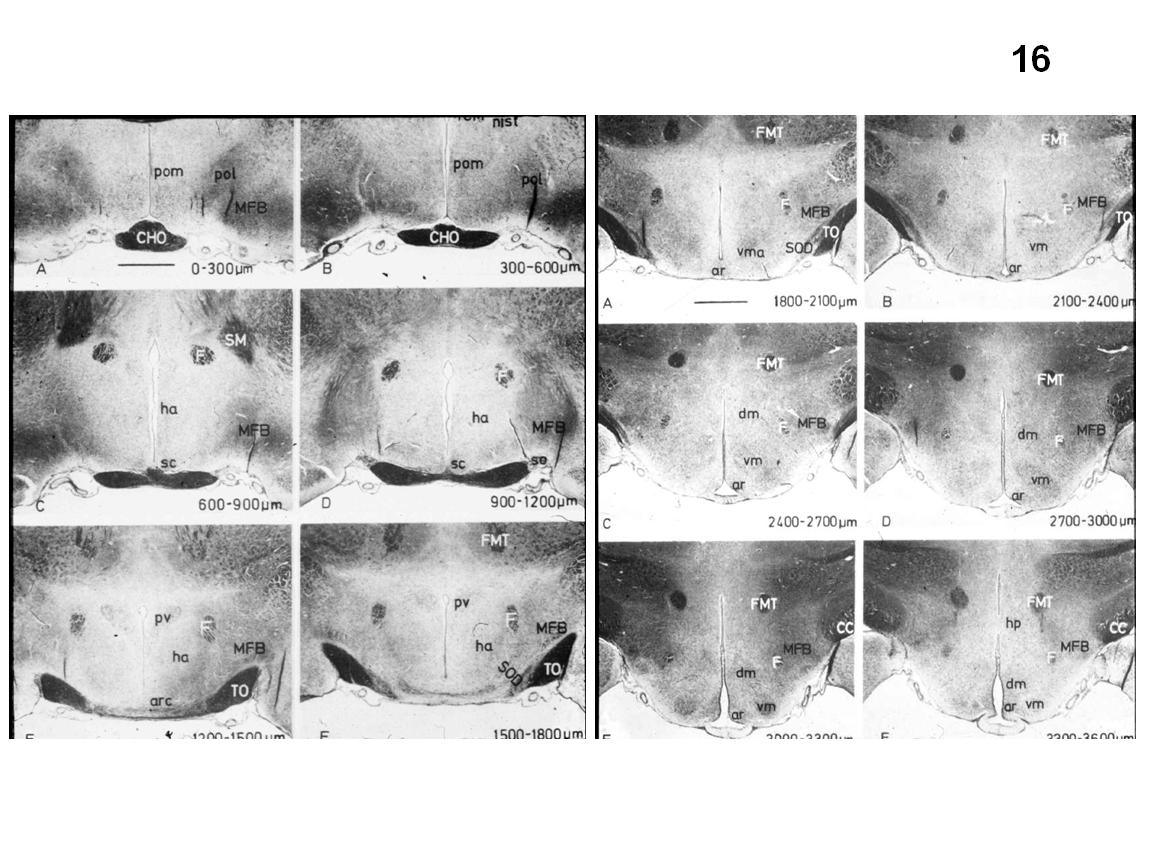

Figure 12 Figure 13 Figure 14 Figure 15 Figure 16 Figure 17